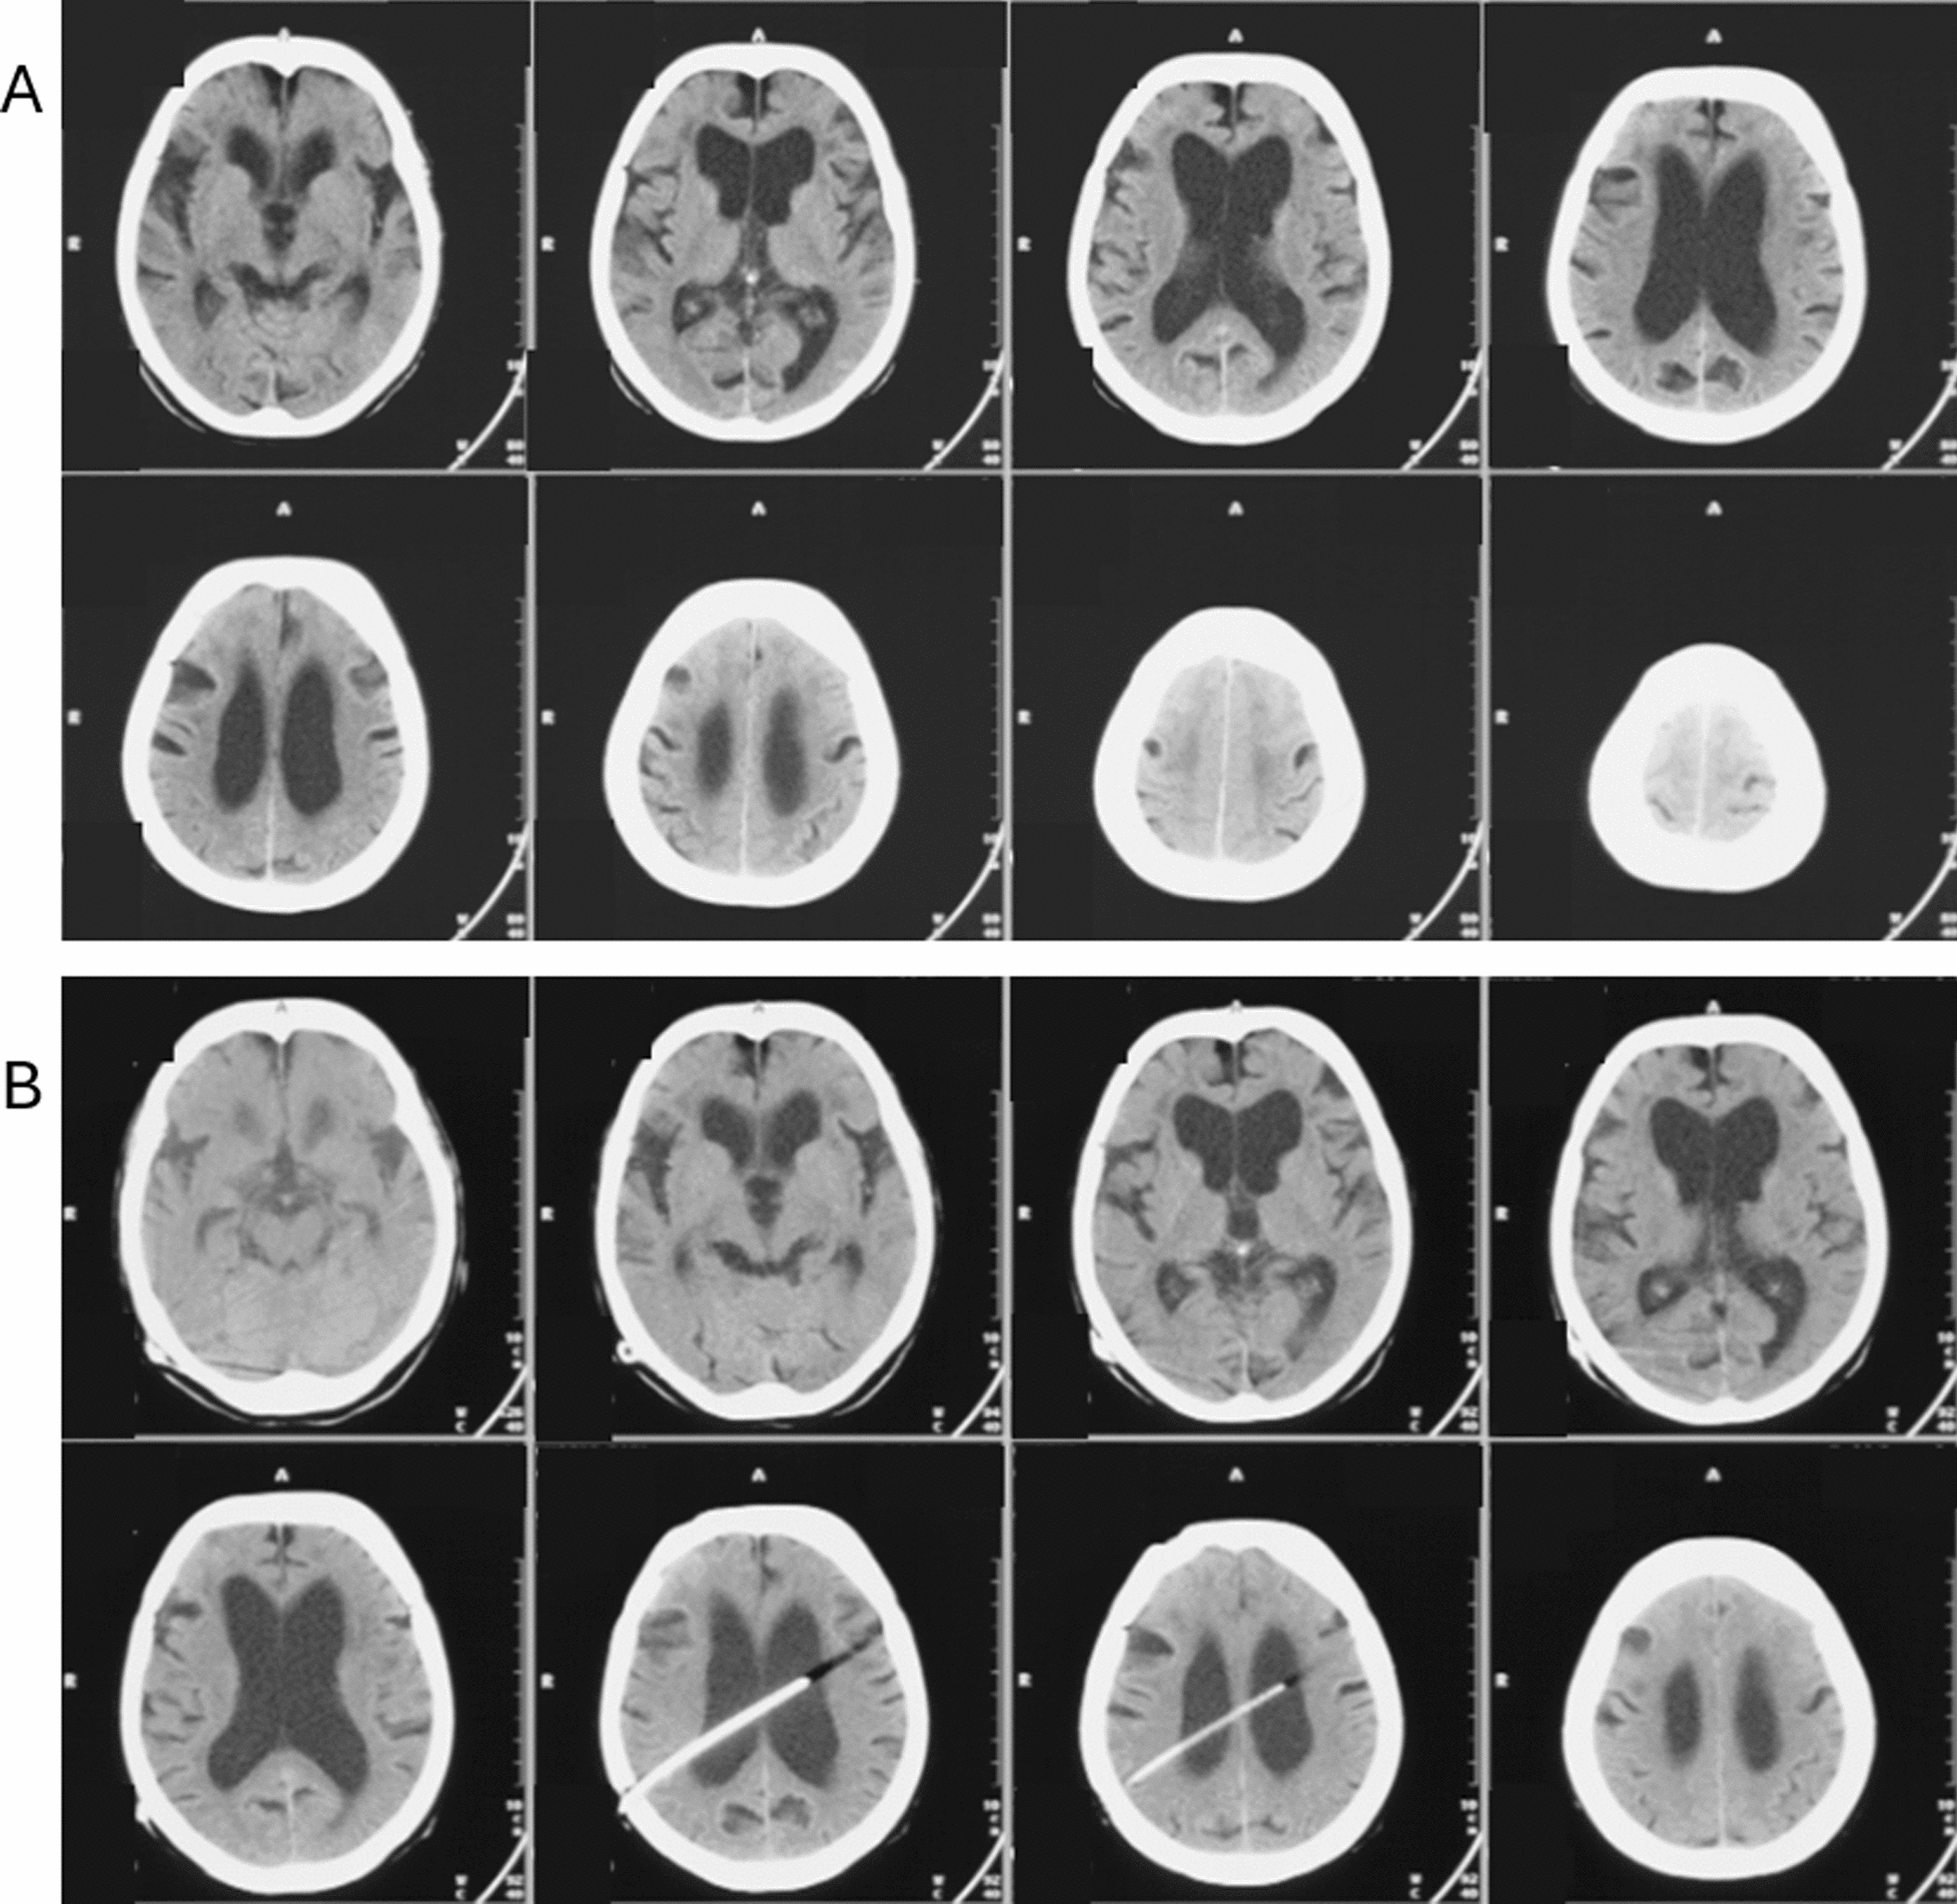

Abstract Image